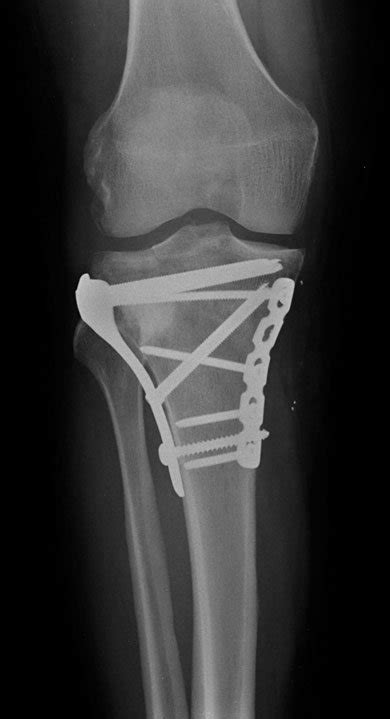

When will i be able to walk without crutches and when will i be able to walk without a limp. After tibial plateau fracture surgery you will experience pain, swelling, stiffness and decreased range of movement in your knee. A fracture is another word for a break. There is normally a recent history of trauma to the knee. People should always follow their doctor's recommendations about returning to walking, exercising, and other physical activity after a leg fracture. Most importantly, by this stage you should not have any residual pain other than an ache and some stiffness when you wake. People are generally unable to walk. (obq09.166) a large posteromedial tibial plateau fracture pattern, as seen with the bicondylar tibial plateau fracture shown in figures a and b, is important to recognize because of which of the following factors? He didn't give me any other instructions other than i worked the next several weeks on my limp and stamina. Tibial plateau fracture with metal plate fixation. Tibial fractures are common and usually caused by an injury or repetitive strain on the bone. Tibial plateau fractures occur just below the knee joint and can involve the cartilage surface of the knee. At this stage, after eight weeks of rehab exercise, it's worth trying to determine what someone with a tibial plateau fracture should be able to do and should not attempt to do. Avulsion fracture of margin of lateral tibial plateau just below joint line. Proper identification and management of these injuries will help to restore limb function. Active flexion and passive extension are encouraged for 6 weeks, after which period active. Pcl and lcl associated with medial plateau fracture.